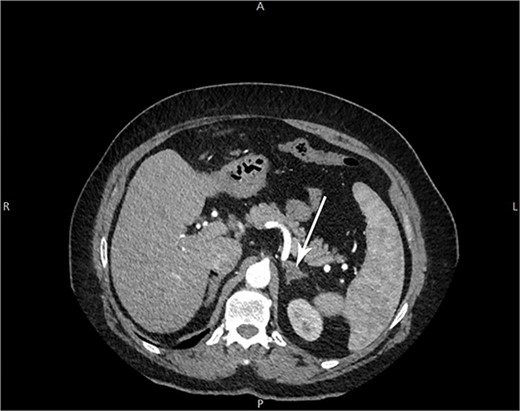

The patient consulted with a physician 2 years ago following failure of laser hair removal therapy done over 8 years. An abdominal and pelvic ultrasound was done which was unremarkable with normal intact ovaries. Contrast Computed Tomography (CT) of the abdomen and pelvis was performed (Fig. 1). It was significant for a non-enhancing hypodense nodule of the left suprarenal gland measuring 1.5 cm in diameter, which was mostly consistent with an adenoma. A 5.5 cm lesion, consistent with liver hemangioma, was seen at the lateral aspect of the right liver lobe.

Arrow: a 1.5 cm non-enhancing hypodense nodule of the left suprarenal gland on CT imaging.